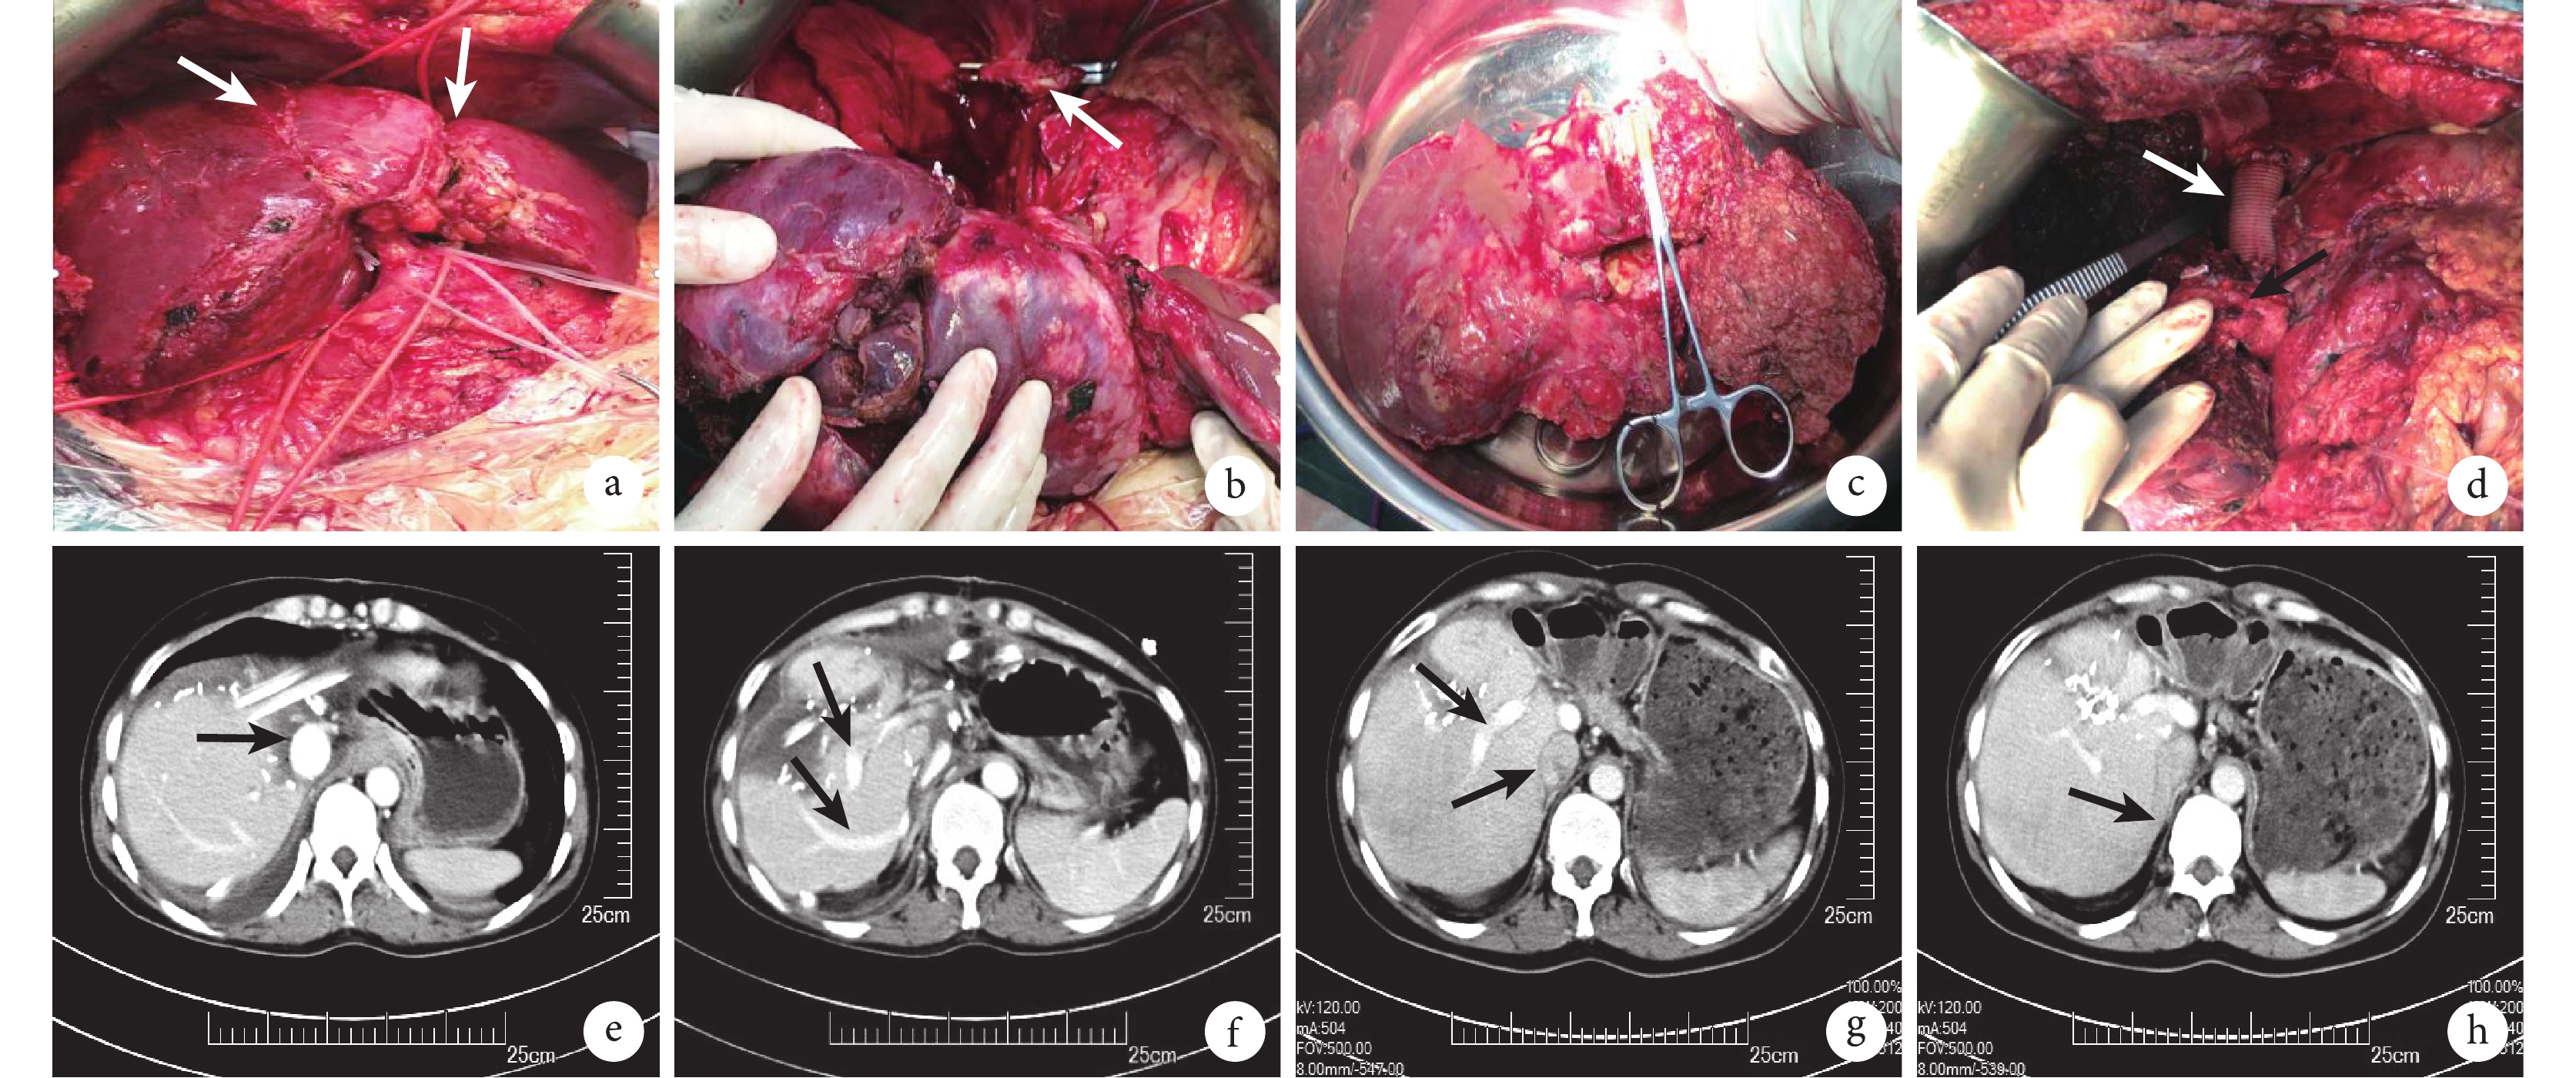

一期手術前:腹部增強 CT 檢查(圖 1a–1f)顯示:肝內見數個大小不等、邊界不清的斑片狀低密度影,局部混雜絮狀稍高密度影,較大者位于肝左右葉交界區(約 9.1 cm×9.4 cm 大),病灶侵蝕 3 支肝靜脈,并包裹壓迫 IVC,可見引流 S6 區域的肝靜脈匯入 IVC;增強后動脈期未見強化,腹腔內及腹膜后未見腫大淋巴結。CT 三維重建(圖 1g 和 1h)示:虛擬切除后功能殘肝體積為 232.6 mL,占標準肝體積的 24.9%。腹部 MRI 檢查顯示:肝臟實質內見多發片樣稍長 T1 不均性 T2 信號影,受累范圍廣,鄰近走行的膽管被包裹,左肝管及其分支擴張,梗阻平面位于左肝管主干區。影像學檢查未見肝外轉移病灶。

a:病灶侵犯第二肝門處肝靜脈(黑箭);b:左肝內葉、右后上段及右前上段可見病灶及擴張的膽管(黑箭);c:IVC 被包裹壓迫(左黑箭)且左側膽管擴張(右黑箭);d:左肝外葉及右后上段肝臟可見病灶,門靜脈右支完整(上黑箭),引流右肝后葉的肝靜脈匯入 IVC(下黑箭);e:引流右肝后下段的肝靜脈(黑箭);f:S6 的截面(綠色區域);g:CT 三維重建圖像的正面觀,見病灶的分布及與第一肝門的關系;h:CT 三維重建圖像的背面觀,見病灶與第二肝門及 IVC 的關系,S6 可見完整的肝靜脈流出道;i 和 j:病灶侵犯第二肝門處肝靜脈,可見左外葉劈裂口;k:可見兩處劈裂口(白箭)以及膽道引流管(黑箭);l 和 m:門靜脈右支完整,引流右肝后葉的肝靜脈匯入 IVC(黑箭);n:S6 的截面(綠色區域);o:CT 三維重建圖像的正面觀,見病灶較前無明顯變化,殘余肝臟體積明顯增長;p:CT 三維重建圖像的背面觀,見病灶與第二肝門及 IVC 的關系,S6 區域肝靜脈流出道完整

二期手術前:腹部 CT 檢查(圖 1i–1n)顯示:肝臟多發稍低密度團塊及結節,最大者位于肝左右葉交界區,病灶較前無明顯變化,可見左側膽道內引流置管及第一階段手術劈裂口;引流 S6 區域的肝靜脈匯入 IVC。CT 三維重建(圖 1o 和 1p)示:虛擬切除后功能殘肝體積為 450.8 mL,占標準肝體積的 48.3%。影像學檢查未見肝外轉移病灶。

二期手術:① 患者取平臥位,全身麻醉后取上腹“人”字形切口,進腹后腹腔粘連較重。給予胃網膜右靜脈置管,測量門靜脈壓力值為 13 mm Hg。② 游離肝周韌帶,完整顯露肝上腔靜脈及右側肝副靜脈匯入處的肝后下腔靜脈。于第一肝門、肝上腔靜脈及肝后下腔靜脈分別預置阻斷帶(圖 2a)。③ 沿 S6 以電刀劃出預切割線,在術中超聲的輔助下,沿血管走行劈裂肝臟,注意辨別并保留右肝后下段的 Glisson 鞘及肝副靜脈完整。然后離斷右肝后上葉、右肝前葉及左肝 Glisson 鞘,此時 S6 獨立于肝臟其余部分。④ 阻斷肝上腔靜脈,血流動力學未見明顯變化,自肝副靜脈-腔靜脈匯合處上方阻斷腔靜脈,于上下阻斷處離斷腔靜脈(圖 2b),取出由 S1、S2、S3、S4、S5、S7 及 S8 組成的手術標本(圖 2c)。⑤ 運用自體肝移植技術,使用直徑 2 cm、長約 8 cm 的人工血管重建切除段的 IVC(圖 2d),分別于 IVC 的上下殘端以 5-0 Prolene 血管線行連續吻合。開放血管后吻合口無明顯滲血,門靜脈壓力值為 13 mm Hg。于 winslow 孔和殘肝斷面前后各放置 1 根腹腔引流管,自腹壁引出,常規關腹。

a:解剖肝固有動脈、膽總管、門靜脈及 IVC 并標記,可見一期手術兩處劈裂口(白箭);b:離斷肝上及肝副靜脈匯入處之間的 IVC(白箭);c:切除由 S1、S2、S3、S4、S5、S7、S8 和部分 IVC 組成的手術標本;d:人工血管(白箭)重建離斷的 IVC 部分,見右后下段 Glisson 鞘(黑箭);e:肝臟形態正常,人工血管通暢(黑箭);f:術后殘余肝臟門靜脈(上黑箭)及肝靜脈回流通暢(下黑箭);g:肝臟形態正常,肝臟 IVC(下黑箭)及門靜脈通暢(上黑箭);h:肝靜脈回流通暢(黑箭)

二期手術:手術時間 700 min,出血量 800 mL,術中輸注紅細胞懸浮液 2 U,術后 4 d 轉入普通病房治療,予以保肝、抗感染、抗凝等對癥支持治療。同時予以低分子肝素抗凝,期間監測 INR 值并控制在 1.5~2.5。術后無膽汁漏、出血、感染等并發癥發生,術后 1 周行 CT 檢查(圖 2e 和 圖 2f)示:肝臟流入、流出道通暢,IVC 無狹窄,無血栓形成。于術后 10 d 出院。

出院后規律口服阿苯達唑 [15 mg/(kg·d)] 抗包蟲治療,并口服華法林抗凝治療半年。目前已隨訪 18 個月,患者的一般狀況良好,CT 檢查(圖 2g 和圖 2h)示肝臟及血管無異常,無包蟲復發及其他并發癥發生。